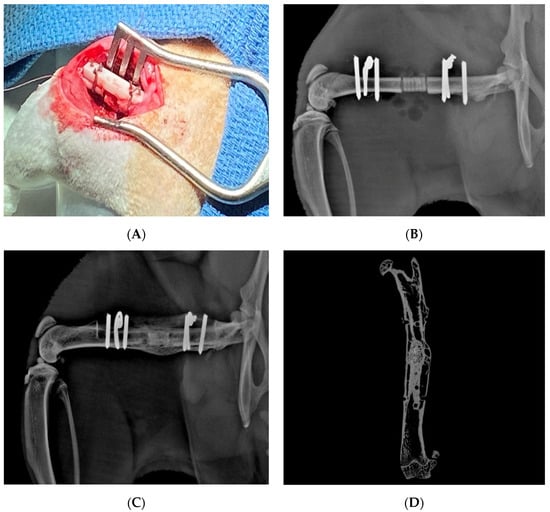

Figure 6.

3D printed hydroxyapatite/tricalcium phosphate scaffold loaded with LV-TSTA-BMP-2 transduced rat bone marrow stem cells. (A) Intra-operative implantation of the scaffold into a 6 mm femoral defect in a Lewis rat. (B) Lateral X-ray image of implanted scaffold on postoperative day 0. (C) Lateral X-ray and (D) MicroCT images taken at 24 weeks demonstrating healing of the defect and incorporation of the scaffold.